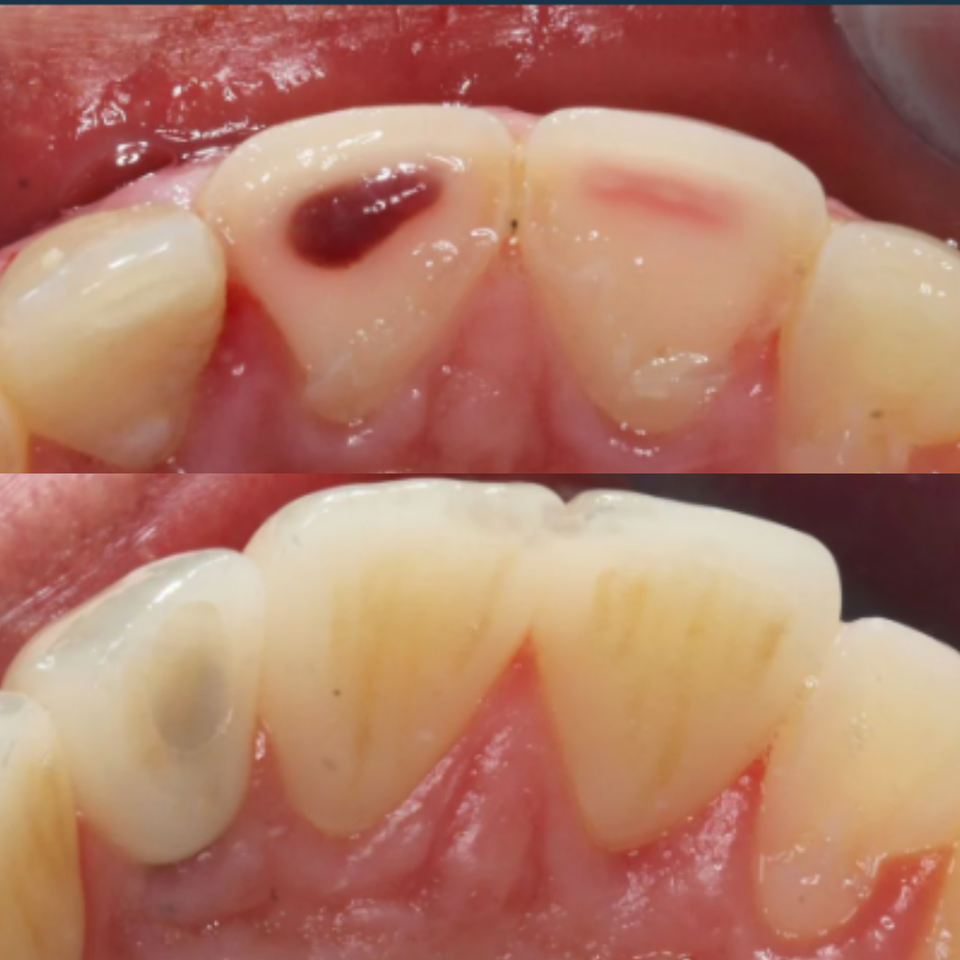

This patient presented with significant gum recession affecting the right central tooth, which ultimately required extraction.

Our team carefully planned and executed the placement of an implant supported crown to achieve a natural looking, fully functional esthetic result. The final outcome not only restored the patient’s smile, but also renewed their confidence.